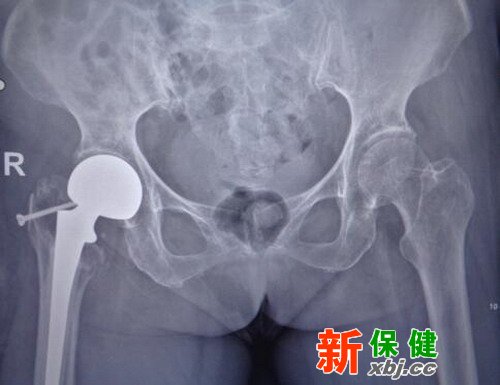

9月17日夜間她獨(dú)自一人在家中上廁所時(shí)不慎摔倒,傷后不能站立,第二天其家人將她送到了醫(yī)院診治。醫(yī)生為她做了X線及髖關(guān)節(jié)CT檢查,診斷為右股骨粗隆間粉碎骨折。

區(qū)奶奶有高血壓病史,長期自服降壓藥。入院后醫(yī)務(wù)人員為她監(jiān)測血壓血糖,完善各項(xiàng)檢查,并進(jìn)行圍手術(shù)期處理,經(jīng)醫(yī)務(wù)人員討論決定,擬行右側(cè)人工股骨頭置換術(shù)。

術(shù)前

廣州和平骨科醫(yī)院骨科主任、副主任醫(yī)師胡鐵山介紹,手術(shù)難點(diǎn)在于區(qū)奶奶是高齡患者,而且有高血壓病史及糖尿病史,股骨大轉(zhuǎn)子粉碎,解剖結(jié)構(gòu)發(fā)生了改變,截骨平面無對照,骨質(zhì)缺損大,假體固定困難,要進(jìn)行人工股骨頭置換術(shù),難度高風(fēng)險(xiǎn)大。憑著多年的手術(shù)經(jīng)驗(yàn),骨科胡鐵山主任、王亮醫(yī)生和郭志剛醫(yī)生在硬膜外麻醉下為區(qū)奶奶做了“右側(cè)人工股骨頭置換術(shù)”,手術(shù)非常順利。

術(shù)后

在護(hù)理上,醫(yī)院術(shù)后給予區(qū)奶奶預(yù)防感染、抗凝、預(yù)防深靜脈栓塞及對癥治療,指導(dǎo)與加強(qiáng)術(shù)后康復(fù)鍛煉。目前區(qū)奶奶恢復(fù)良好,術(shù)后第三天可站立及行走,復(fù)査拍片提示人工假體位置良好。